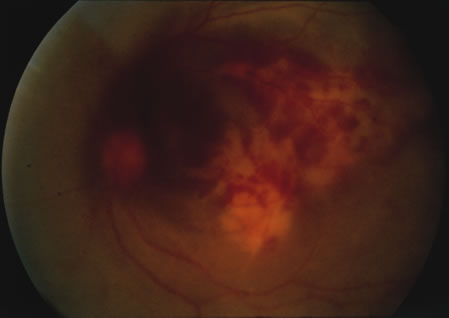

Even less common than retinopathy is lupus choroidopathy, of which only a few cases have been reported to date.214,224–226 Early autopsy studies demonstrated the frequent presence of mononuclear inflammatory cells in the choroid of patients with untreated SLE.208 The clinical changes seen in patients with lupus choroidopathy include serous elevation of the retina, most often of the neurosensory retina, serous elevations of the retinal pigment epithelium, and combined elevations of both (Fig. 7). These clinical findings are associated with systemic vascular disease, either hypertension because of lupus nephritis or systemic vasculitis.226 Treatment of the underlying disease, with systemic corticosteroids and immunosuppressive agents if needed, and control of any hypertension can resolve these serous retinal detachments.

Fig. 7. A. Fundus photograph and B. and C. fluorescein angiogram of a patient with choroidopathy and systemic lupus erythematosus. The fluorescein angiogram demonstrates multiple “smokestack” areas of fluorescein leakage. (Jabs DA, Hanneken A, Schachat AP, et al: Choroidopathy in systemic lupus erythematosus. Arch Ophthalmol 106:230, 1988. Copyright 1986, American Medical Association. Reprinted with permission.)